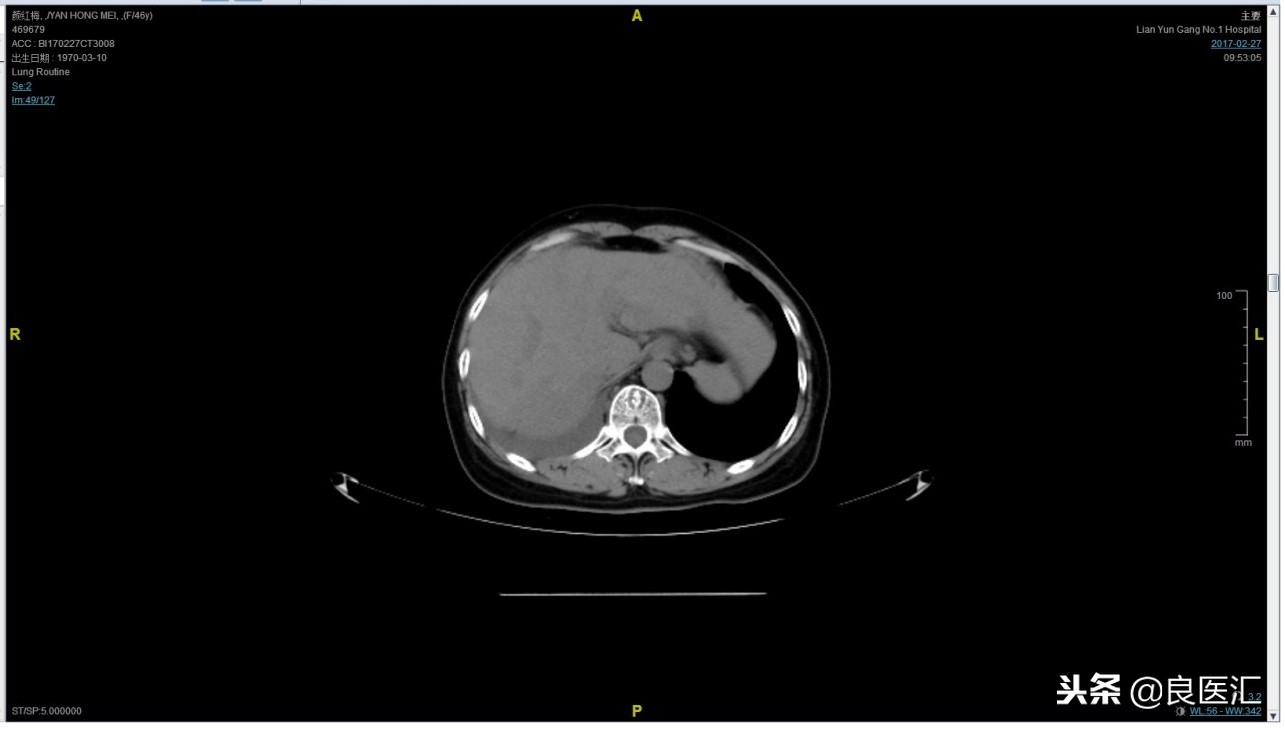

2017-02-27患者因气喘胸闷再次就诊。患者肺部病灶进展,同时出现肝脏转移。再次给予曲妥珠单抗+长春瑞滨化疗一周期,效果不佳,推荐换用TKI治疗,患者放弃治疗。PFS3=12个月。